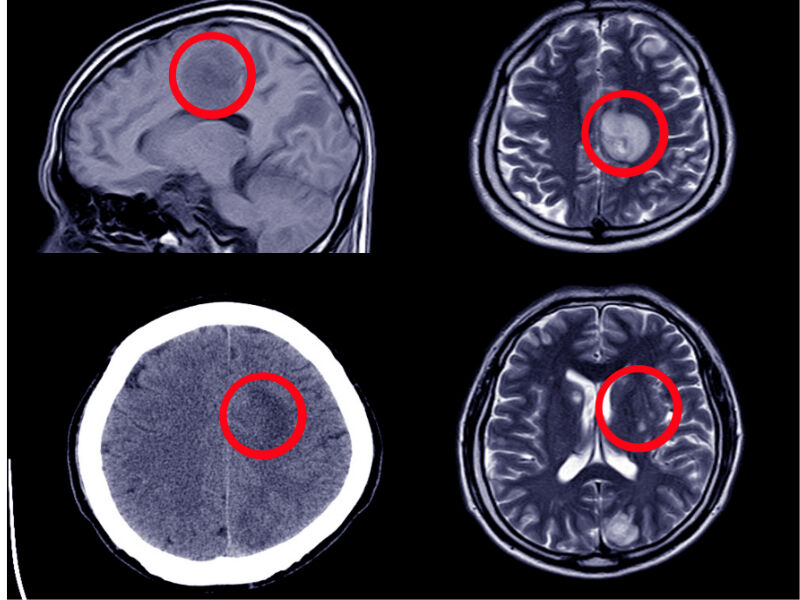

Aslında K vitaminine bağlı olarak gelişen intrakranial kanama önlenebilir bir hastalık. Böyle bir hastalıktan nörolojik sekelle kalacak ya da kaybedilecek bir hastanın olması üzüntü verici.

2012 yılında bölüm olarak yaptıkları bir çalışmada K vitamini eksikliği nedeniyle 120 hastanın 31’inin öldüğünü 73’ünün de beyin kanaması geçirdiğini ifade eden Per, "2012 yılında Çocuk Nöroloji ve Çocuk Hematoloji bölümü öğretim üyeleri ile beraber yaptığımız bir çalışma var. Bu çalışma 120 hastalık bir çalışma. Literatürdeki en geniş çalışmalardan bir tanesi. Bu çalışmamızda hastalarımızı yüzde 31’i vefat etmiş. Biz bu çalışmamızı 1990 ila 2006 yılları arasında hastanemize gelen K vitaminine bağlı intrakranial kanaması olan hastalarda yaptık. O zaman çarpıcı olan hastaların neredeyse 4’de 1’i evde doğum olmuştu. Evde doğum yapılınca K vitamini aşısı yapılmadığı için K vitamini eksikliğine bağlı olarak intrakranial kanama riski daha yüksek oluyor. 120 hastanın 81’i hastanede doğmuştu. O dönem için evde doğumlar yapılıyordu ama artık Türkiye’nin hiçbir yerinde evde doğum yapılmıyor ya da çok az yapılıyor. Bizim 120 hastamızın yüzde 73’ünce beyin kanaması vardı. Beyin kanaması olunca hastaların ya büyük bir kısmı ölüyor ya da nörolojik sekelle kalıyor. 2012 yılında bu çalışmamız yayınlandı” dedi.

"BİR TARAFTA ÖLÜM, DİĞER TARAFTA NÖROLOJİK SEKEL"

K vitamininden mahrum bırakılan bebeklerin yüksek oranda nörolojik sekelle ya da ölümle karşı karşıya kaldığını ifade eden Per; “Bir süre sonra beyin cerrahiden, çocuk hematolojiden ve çocuk nöroloji bölümünden arkadaşlarımızla yaptığımız ve bir dergide yayınlanan makalemizde tüm Türkiye’deki K vitamini eksikliğine bağlı intrakranial kanamaları topladık. 534 vakada K vitamini eksikliğine bağlı olarak kanama olmuş. Bunlardan yaklaşık 414’ü yani yüzde 77’si beyin kanaması ile gelmiş. Bu çok büyük bir oran. 3 tip K vitamini eksiliği var. Bir tanesi erken dönem K vitamini eksikliği, ikincisi ilk bir haftada ortaya çıkan klasik K vitamini eksikliği daha sonrasında ise geç K vitamini eksikliği 6 aya kadar uzayabiliyor. Bununda en önemli neden bağırsaklarda yeterince K vitamini yapılamaması. Eğer bir de siz bu eksik olan K vitaminini vermezseniz, çocuklar sadece anne sürüyle beslendiği zaman ortaya çıkabilecek bir ishalde ya da enfeksiyonlarda çocuklarda K vitaminine eksikliğine bağlı intrakranial kanama olmaktadır. Türkiye’de yapılan çalışmadaki 534 vakanın yüzde 20’si ölmüş. Bunu yüzde 48’i de nörolojik sekelle kalmış. Bir tarafta ölüm, diğer tarafta nörolojik sekel var” diye konuştu.